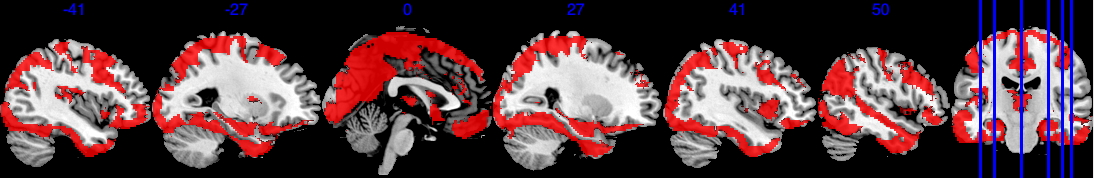

To define the analysis mask, we recall the definition of observed proportion (OP) at location to be , where is the set of all observed locations for individual . We define the group analysis mask as , i.e., the area where each voxel has at least 50% observed data. As shown in Figure 2, the group analysis mask with completely observed data (purple area) covers significantly less area compared to , which has at least 0.5 observed proportion (blue area). In the complete observed data, large portions of the brain regions are missing, notably including the orbitofrontal cortex, the inferior temporal cortex, and the amygdala—regions crucial for emotion processing. In particular, the mask with complete observed data contains only 52 out of the 110 regions in the Harvard-Oxford atlas.

After applying a common mask with an observed proportion of 0.5, we end up with that contains voxels. The image outcomes are standardized across subjects, i.e. where is the original image for subject location , is the sample mean, and SD[M(s)] is the standard deviation of . For each region, we apply the Matérn kernel function but with different and parameters (6), to account for the different smoothness of each region. Both and are determined through grid search so that the empirical covariance of and the estimated covariance by the Matérn kernel have the smallest difference in Frobenius norm. The number of bases is chosen so that the cumulative summation accounts for 90% of the total summation of all eigenvalues, hence we have a total number of . In Section 4.4.1, we provide a sensitivity analysis when the cutoff is based on 92% of the total summation.